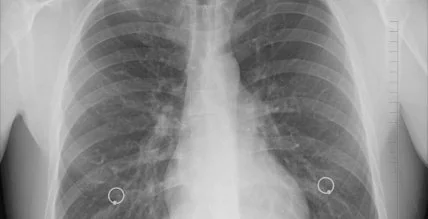

Рак легких является одной из наиболее распространенных форм рака.

За многие годы врачи научились бороться с этим заболеванием. Главное, вовремя диагностировать рак легких и принять необходимые меры, чтобы избежать летального исхода. О начале развития болезни свидетельствуют некоторые симптомы, заметив хоть один из которых, необходимо срочно обращаться за помощью.